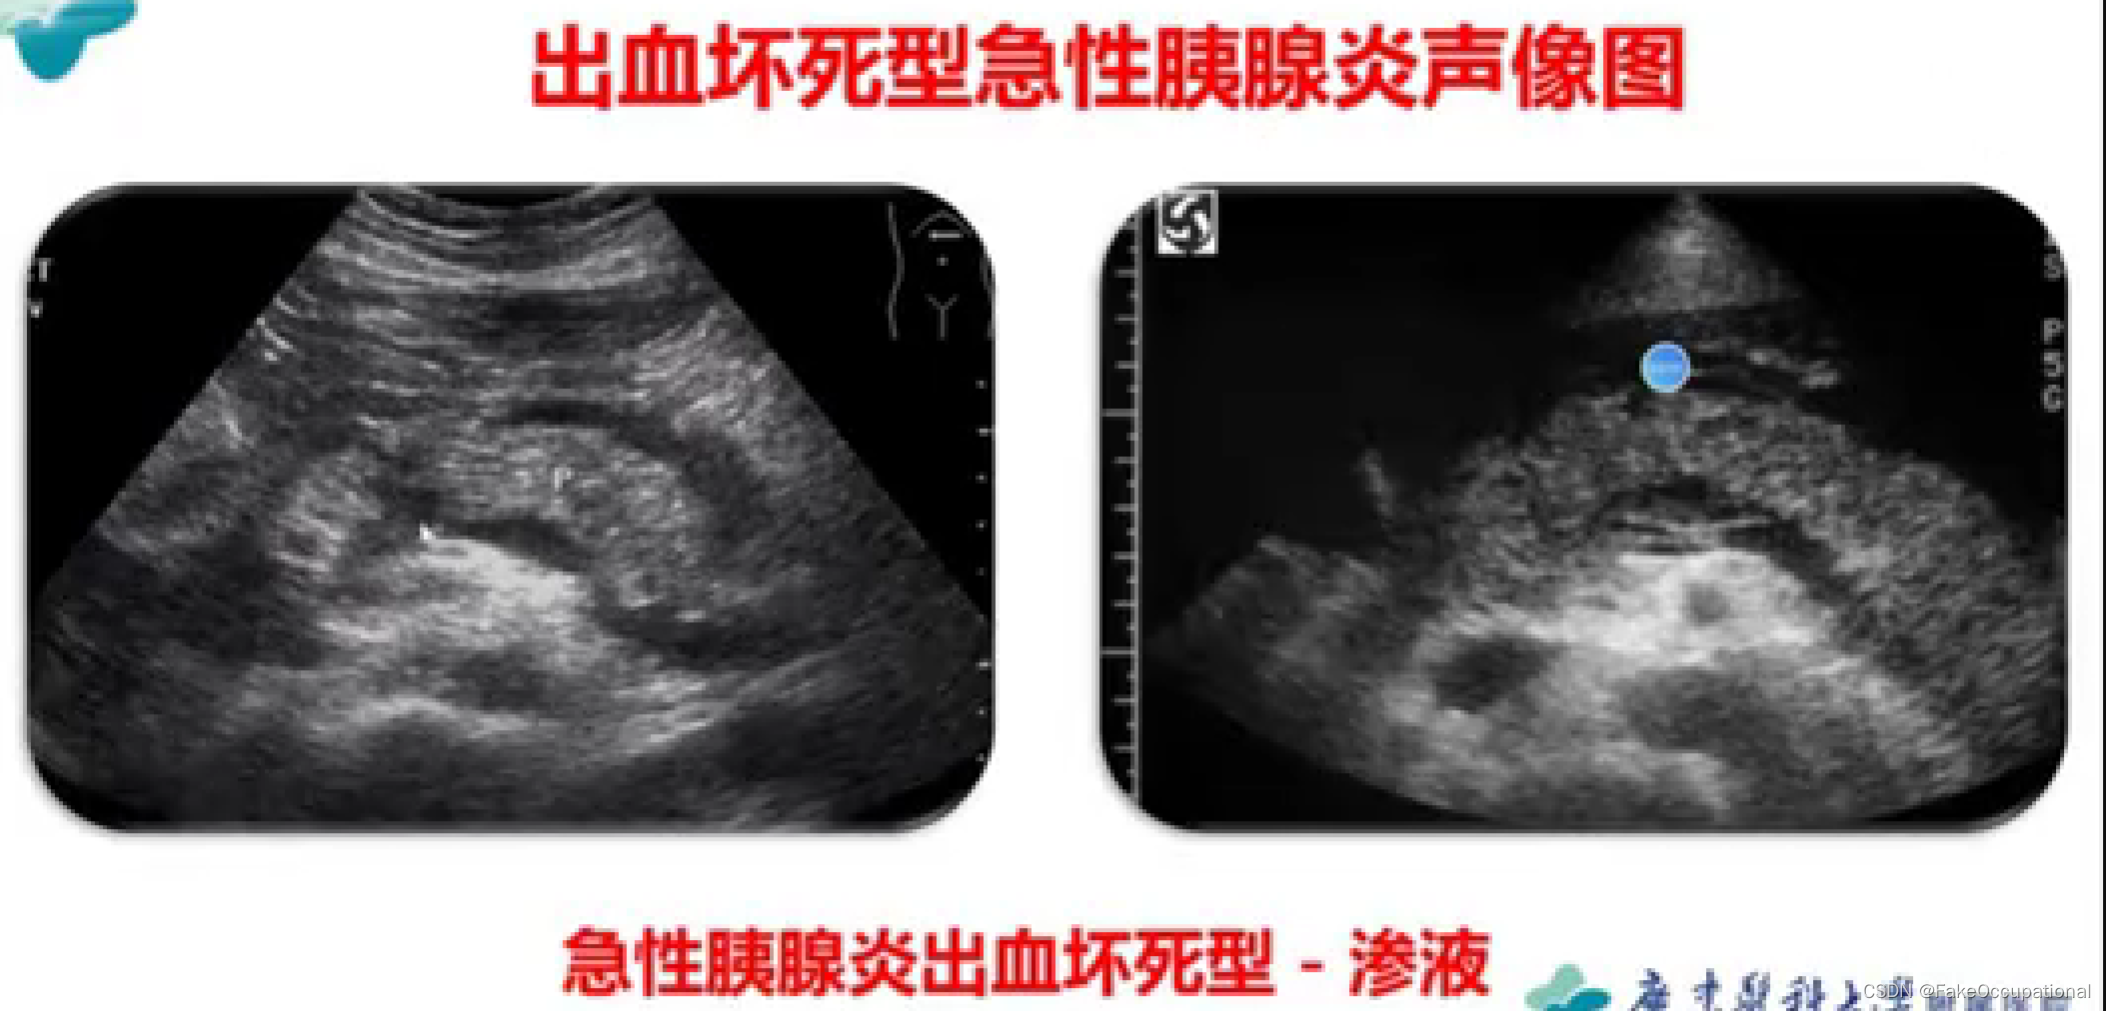

胰腺炎 — 急性胰腺炎、慢性胰腺炎